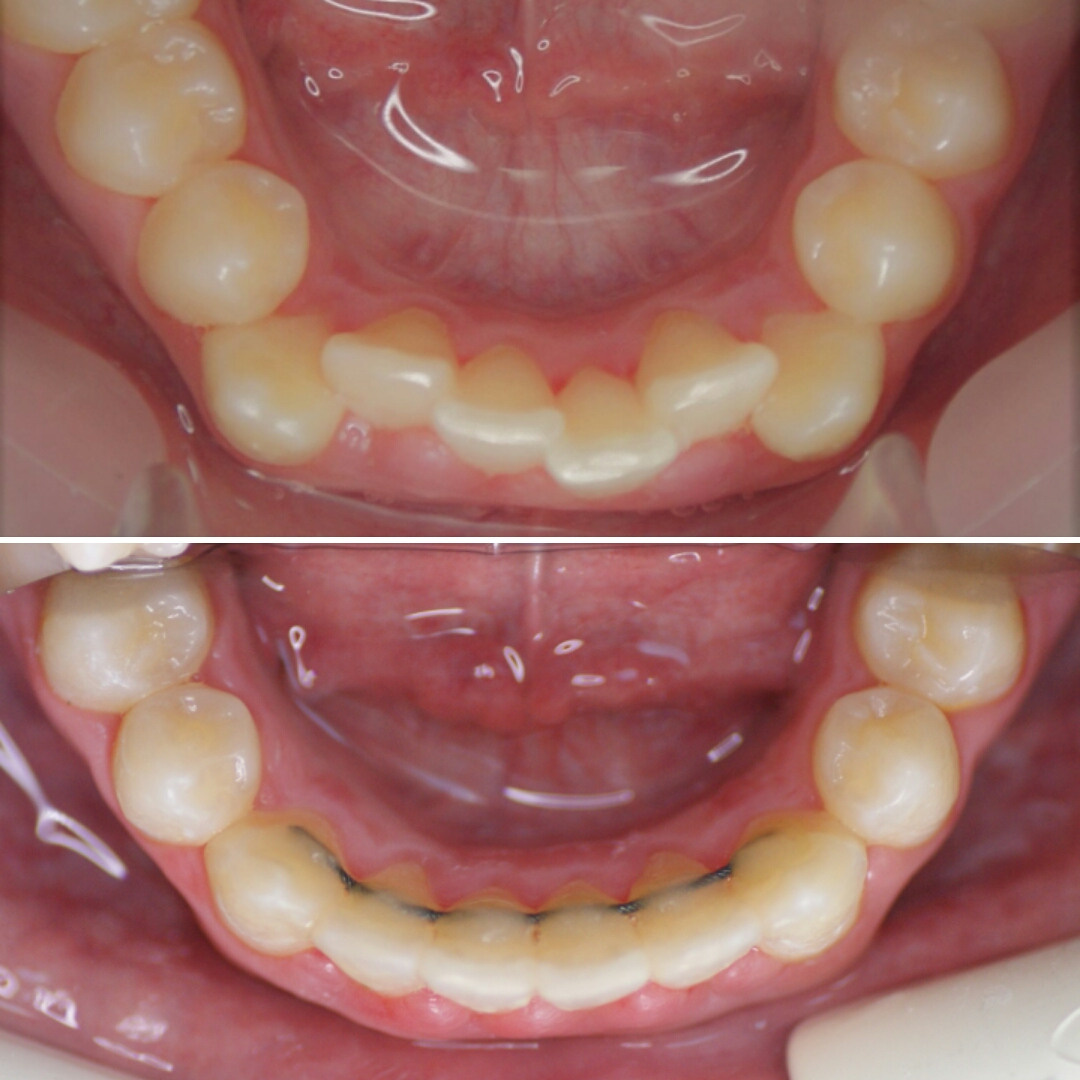

РОДИТЕЛИ! Обратите внимание на МОЛОЧНЫЙ прикус вашего ребёнка!

Зачем?! Да, в возрасте 2-3х лет уже можно заподозрить неладное в челюстно-лицевом развитии.

Как должно быть:

1) Широкие промежутки между всеми молочным зубами говорят о хорошем росте челюстей, о том, что запас места для постоянных зубов есть.

2) Наклоны зубов прямые, зубы не вдавлены внутрь, как на первой фотографии. Правильный наклон обеспечивается правильным положением языка и хорошим жеванием.

3) Бугры клыков и боковых зубов, а также режущие края передних зубов должны стираться. Если зубы острые, значит ребёнок не жуёт. Острые бугры блокируют плавные движения челюсти и ограничивают рост. Надеюсь, понятно. ПРОВЕРЯЙТЕ!